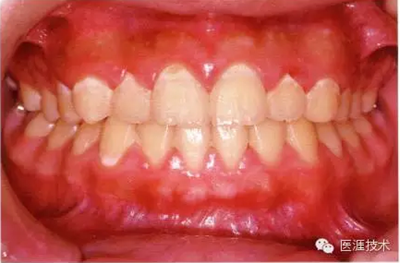

健康且正常的牙周組織臨床圖像

50歲女性的健康口腔內(nèi)部

圖為50歲女性,無特殊全身疾病,不抽煙。持續(xù)保養(yǎng)6年。無填充物等問題,依照患者本人要求持續(xù)觀察。牙周組織臉頰側(cè)雖見部分萎縮,但X線牙片顯示牙間無骨吸收現(xiàn)象,保持著比較健康的狀態(tài)。